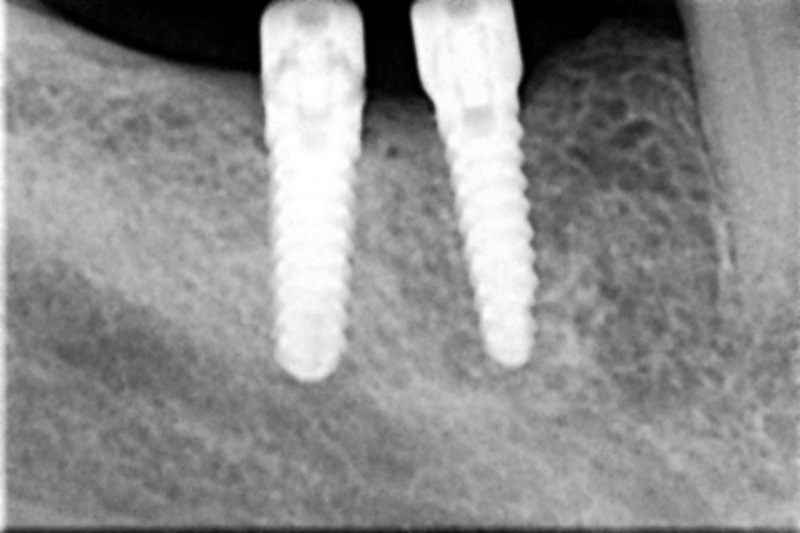

Náhrada jednoho zubu pomocí implantátu je možná také v postranním úseku chrupu. Při ztrátě většího počtu zubů ve frontálním nebo postranním úseku může být mezer uzavřena větším počtem jednotlivých implantátů.

Při ošetření pomocí jednotlivých implantátů zůstávají sousední zuby neporušené – intaktní. Při klasickém ošetření pomocí můstků musejí být tyto zuby obroušeny!